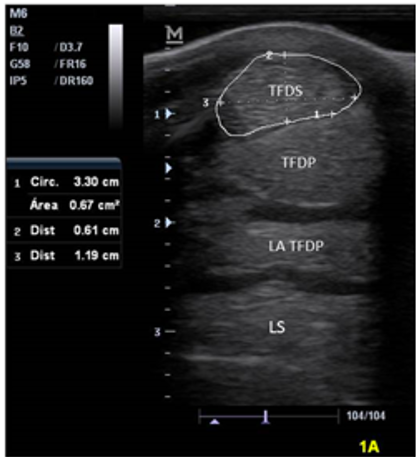

In all the animals, the ultrasound evaluation was performed by the same operator to avoid possible inter-operator variations (12). Transverse ultrasound images (dorsal anatomical plane) of the metacarpal region were obtained in the palmar aspect (Zone 1A, 1B, 2A, 2B and 3A). The ultrasound examination was performed with a mobile ultrasound equipment (Mindray M6, 2018, USA) in combination with a linear probe (Mindray) from 8 to 10 MHz and standoff pad. 2 scans in each zone were taken in both limbs, in the last zone 6 scans were taken (palmar, medial and lateral). Structures studied from palmar to dorsal were the tendo musculi flexor digitalis superficialis (Superficial Digital Flexor Tendon SDFT), tendo musculi flexor digitalis profundus (Deep Digital Flexor Tendon DDFT), ligamentum accessorium (accessory ligament DDFT AL) and the body of the musculus interosseus medius (Suspensory Ligament SL), and also the medial and lateral branches of the SL (6).

Measurements. Measurements were made of the images obtained using the equipment’s measurement software. The following variables were measured for each structure in each zone: Cross sectional Area (CSA) cm., Latero medial widht (LM), Dorso palmar width (DP). Cross sectional area was obtained by delimiting the borders of each structure, the LM from the most lateral to the most medial point of each structure and the DP from the most dorsal to the most palmar point in all areas equally. The final value for each variable was the mean between the two scans that were taken for each structure; if the coefficient of variation (CV) was> 10%, two new measurements were made (3).

Values of the morphometric measurements of the metacarpal flexor tendons and ligaments of the study animals are described in table 1. The structures observed in the ultrasound can be seen in figure 2, as well as in figure 3,4,5,6, which describes the behavior of the measurements of the tendons and ligaments studied in each area according to the variables in the 30 horses of the study.